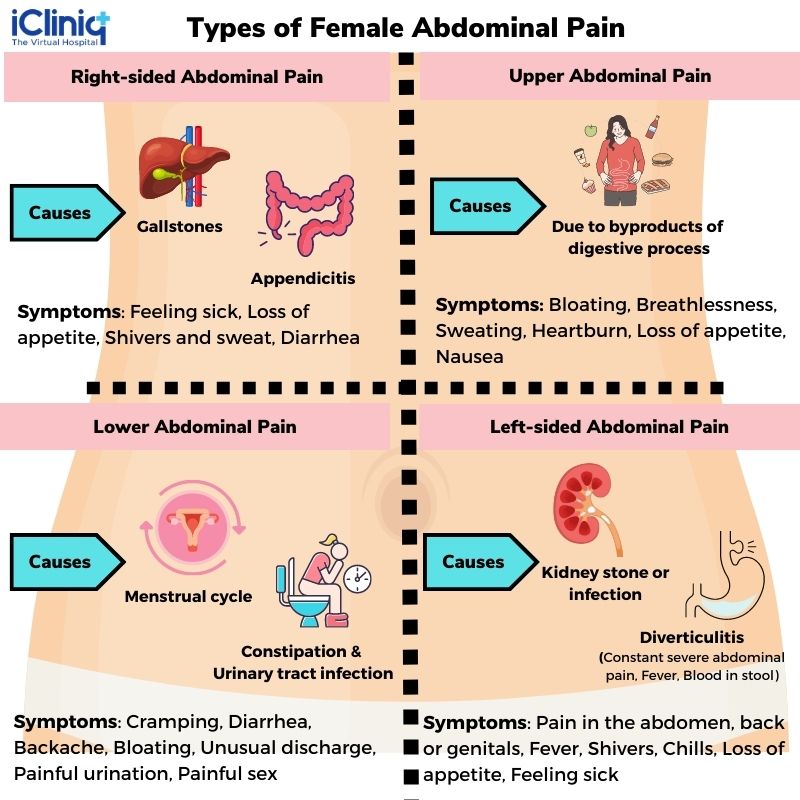

Pin on Abdominal Pain

Pin on Symptoms and Conditions

Causes of Pain in the Right Side | New Health Advisor

Pin on Abdominal Pain Relief | Binders, Braces & Treatments for Stomach …

What Can Cause Right Side Abdominal Pain?

Pin on All about Health

Abdominal and Pelvic Pain in the Nonpregnant Female | Tintinalli’s …

Lower Abdominal Pain: Symptoms And Causes – Forbes Health

Abdominal pain | Health | Pinterest | Pain d’epices and Abdominal pain

Female Abdominal Pain | Types | Symptoms | Causes | Diagnosis | Treatment

What Is Pain In Lower Right Side Of Stomach – StomachGuide.net